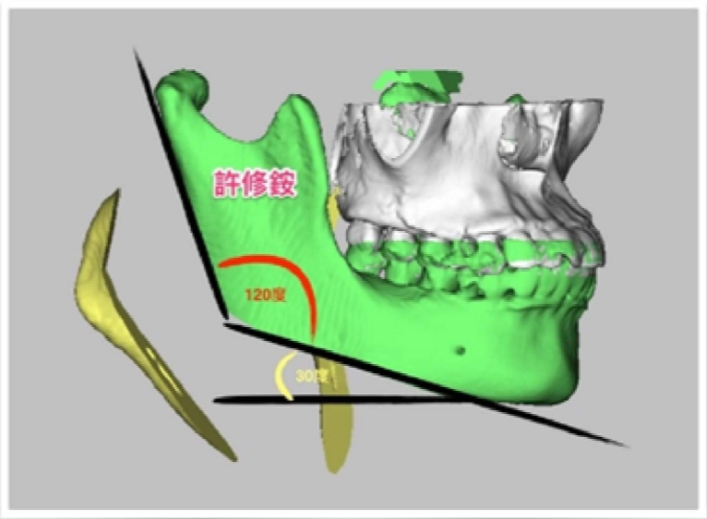

(黃)過度發育之下顎骨角 (黑線)過度平緩下顎下緣

(紅)下顎骨理想角度120度 (黃)下顎平面角想角度30度

骨頭的切除量依據每個人的需求而有不同。但原則是重新塑造理想的下顎骨角角度以符合美觀(約呈120度),且重新建立下顎平面角(約呈30度),改善下臉部過短的視覺效果。